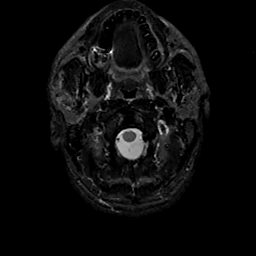

MR Study #11, May 5, 1991 -- Slice #1